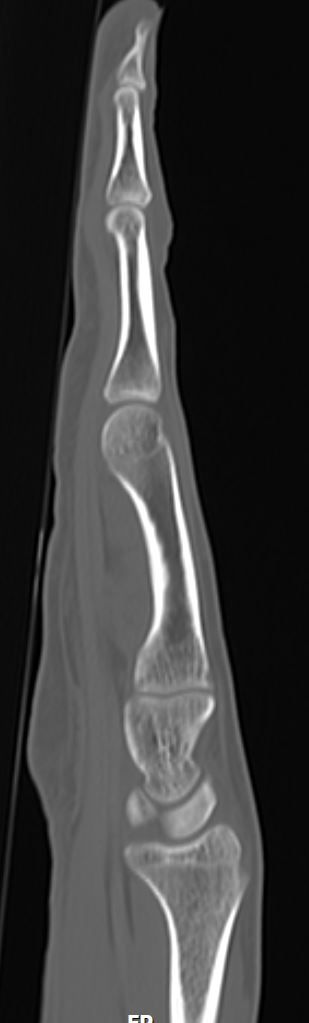

2주전 좌측 3,4수지 손가락이 바깥쪽으로 꺽였습니다.(CT&MRI 사진첨부 했습니다.)

증상은 좌측 제3수지 중지골에 피멍과 통증 그리고 손가락이 안으로 안굽혀 집니다.

골절인지 인대파열인지 아니면 다른 부분이 혹시 보이는지 알려주시면 감사하겠습니다.

• 1번 째 사진